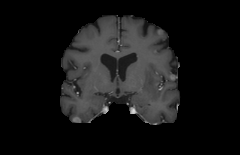

Objectives: This work aims to explore the impact of multicenter data heterogeneity on deep learning brain metastases (BM) autosegmentation performance, and assess the efficacy of an incremental transfer learning technique, namely learning without forgetting (LWF), to improve model generalizability without sharing raw data. Materials and methods: A total of six BM datasets from University Hospital Erlangen (UKER), University Hospital Zurich (USZ), Stanford, UCSF, NYU and BraTS Challenge 2023 on BM segmentation were used for this evaluation. First, the multicenter performance of a convolutional neural network (DeepMedic) for BM autosegmentation was established for exclusive single-center training and for training on pooled data, respectively. Subsequently bilateral collaboration was evaluated, where a UKER pretrained model is shared to another center for further training using transfer learning (TL) either with or without LWF. Results: For single-center training, average F1 scores of BM detection range from 0.625 (NYU) to 0.876 (UKER) on respective single-center test data. Mixed multicenter training notably improves F1 scores at Stanford and NYU, with negligible improvement at other centers. When the UKER pretrained model is applied to USZ, LWF achieves a higher average F1 score (0.839) than naive TL (0.570) and single-center training (0.688) on combined UKER and USZ test data. Naive TL improves sensitivity and contouring accuracy, but compromises precision. Conversely, LWF demonstrates commendable sensitivity, precision and contouring accuracy. When applied to Stanford, similar performance was observed. Conclusion: Data heterogeneity results in varying performance in BM autosegmentation, posing challenges to model generalizability. LWF is a promising approach to peer-to-peer privacy-preserving model training.